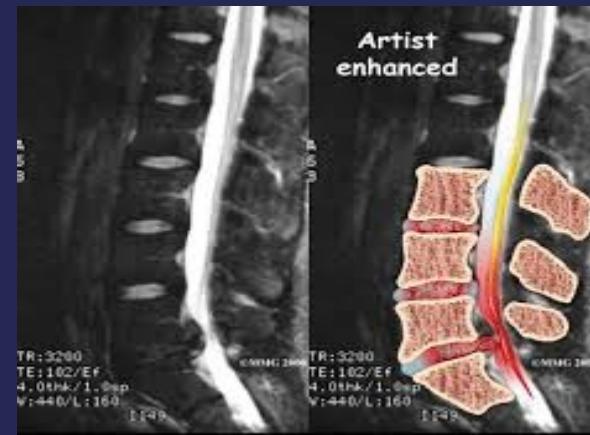

MRI:

- Gold standard for identifying disc pathology and localizing lesions

- Shows:

- Disc sequestration

- Disc bulge/protrusion

- MRI:

- Gold standard for disc identification and lesion localization